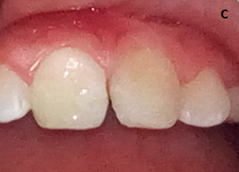

Año y medio después (18 meses) se apreció una evolución clínica favorable con ausencia de signos inflamatorios, VSG y PCR dentro de límites normales. En la a radiografía periapical se observó una adecuada cicatrización del tejido óseo. Se realizó reconstrucción con resina microhíbridas del tercio incisal de ambos incisivos centrales superiores (Figura 2) y se continuó con el seguimiento clínico.

La edad de la paciente, la ausencia de compromiso sistémico y las características del hueso maxilar, fueron factores que favorecieron la remisión de la infección. Después de 18 meses del tratamiento la paciente ha mantenido una evolución favorable, los estudios radiográficos indicaron cicatrización ósea, lo cual permitió conservar los incisivos y su reconstrucción con resina microhíbridas para devolverle la función y la estética.